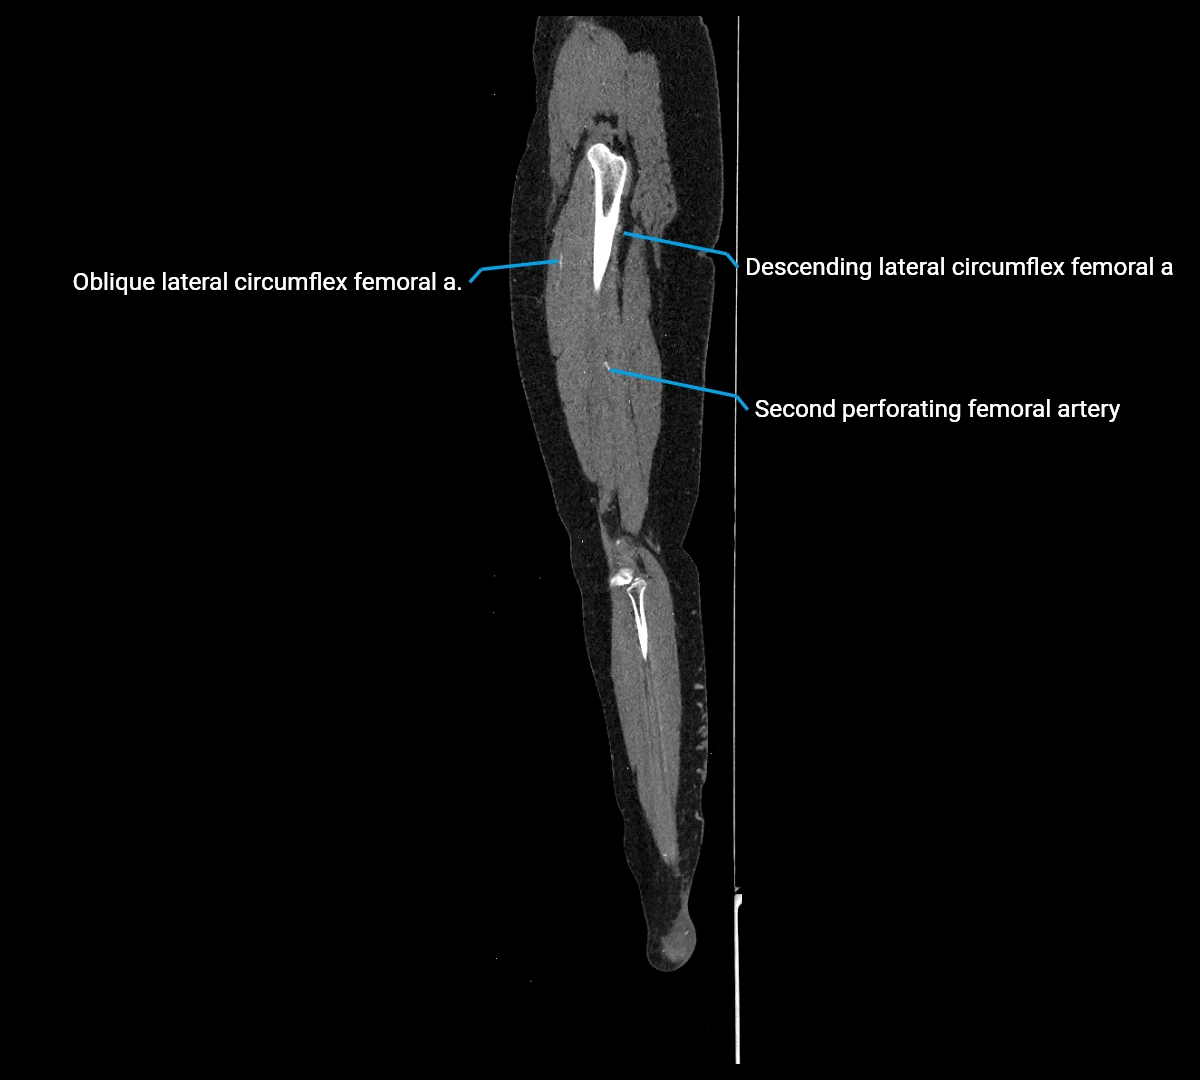

Contrast-enhanced CT (CTA):

• Gold standard for abdominal aortic imaging

• Provides excellent detail of lumen, wall, aneurysm, thrombus, and branch vessels

• Multiplanar and 3D reconstructions help in aneurysm measurement, stent graft planning, and dissection evaluation

• Detects acute rupture, traumatic injury, or occlusion with high sensitivity